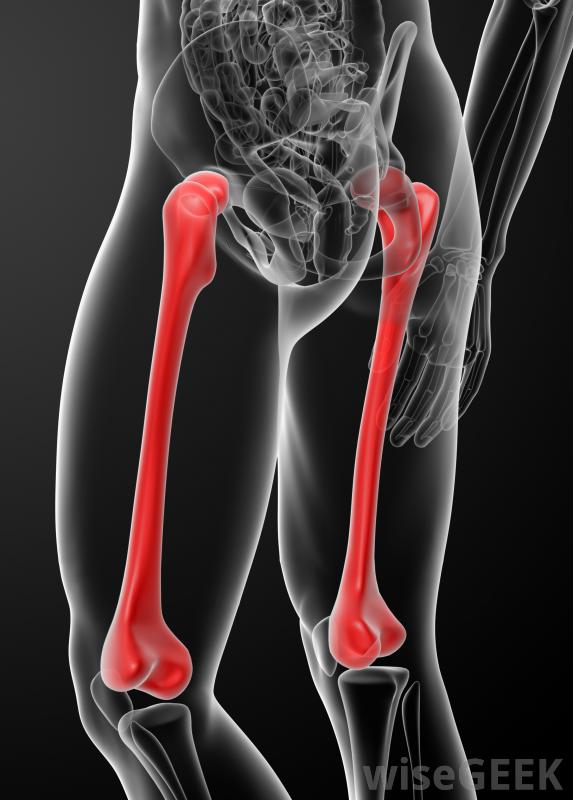

像股骨这样的长骨是骨囊肿常见的地方简单的骨囊肿发生于液体充满骨的空腔时。浆液性液体是空腔中最常见的液体类型,但在某些情况下也可以发现血液。这种囊肿通常被压缩的纤维组织包围

骨囊肿通常发生在长骨上,长骨是指长度超过其宽度的骨头简单骨囊肿最常见的骨骼类型。最典型的简单骨囊肿见于上臂骨(肱骨)和大腿骨(股骨)。此外,这种类型的囊肿倾向于在干骺端形成,这是骨头的一个部分,它的长轴与末端相连